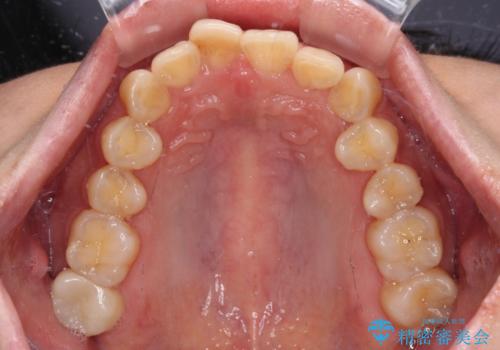

デコボコと乳歯の欠損 ワイヤー矯正とインプラント補綴治療

- 全体的なデコボコと左下乳歯部の欠損を気にして来院された患者様です。

乳歯が抜け落ちた後の後続永久歯が欠損しているため、スペースが残っておりました。

第二小臼歯の欠損によるが乳歯残存や欠損が多く、この乳歯は後続永久歯に比べて幅が非常に大きいため、教聖地料によるスペースクローズが難しいことが一般的です。